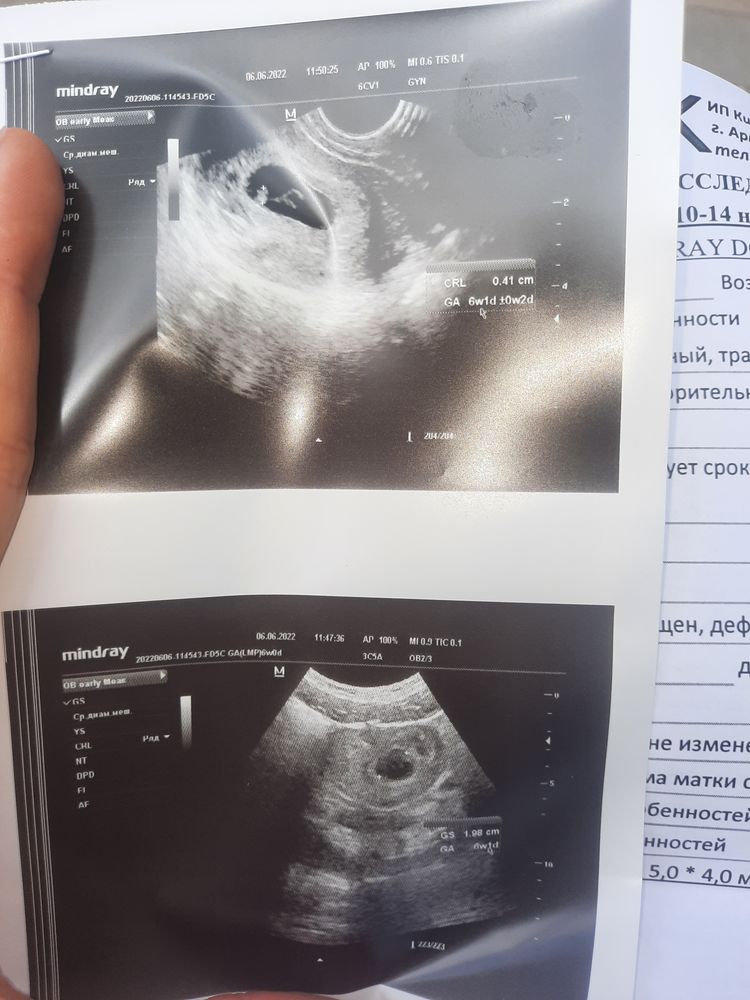

Сходила на узи, подтвердили беременность 6 недель и 1 день .

Беременность срок 6 недель 1 день,но что означает это заключение. У кого было так? Очень переживаю как бы не было угрозой для малыша.

Заключение . Но я так же рада,что я беременна

Заключение